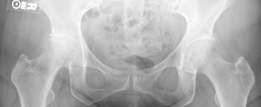

Case Title: Uncemented Primary Total Hip Arthroplasty (Using an Extensively Porous-Coated [Anatomic Medullary…

Demographics Age: 77 Sex: Female BMI: 32 Relevant Past Medical History Principal pathologies: Rheumatoid arth…